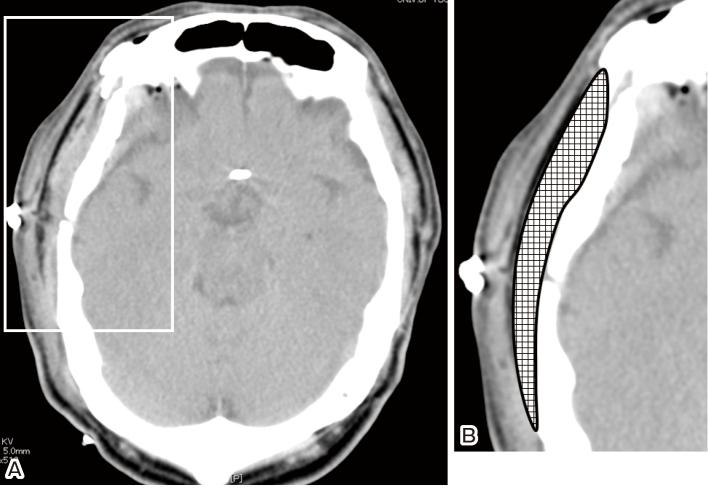

Immediate postcraniotomy headache frequently occurs within the first 48 h after surgery. The mechanisms underlying immediate postcraniotomy headache are not yet fully understood, and effective treatments are not yet established. This study aimed to identify the factors associated with immediate postcraniotomy headache in patients who underwent clipping surgery with frontotemporal craniotomy and to examine the effects of these factors on postcraniotomy headache. A total of 51 patients were included in this study. Immediate postcraniotomy headache was defined as pain with numerical rating scale score ≥4 on postoperative day 7. Sixteen patients (31.4%) had immediate postcraniotomy headache. The headache-positive group had a higher incidence of preoperative analgesic use (50.0% vs. 5.7%, respectively, p < 0.001), increased temporal muscle swelling ratio (137.0%±30.2% vs. 112.5%±30.5%, respectively, p = 0.01), and higher postoperative analgesic use (12.9±5.8 vs. 6.7±5.2, respectively, p < 0.001) than the headache-negative group. The risk factors independently associated with immediate postcraniotomy headache were preoperative analgesic use and temporal muscle swelling by >115.15% compared with the contralateral side in the receiver operating characteristic analysis. Postcraniotomy headache was significantly more common in patients with preoperative analgesic use and temporal muscle swelling than in those without (p < 0.001 and p = 0.002, respectively). Altogether, patients with immediate postcraniotomy headache had greater preoperative analgesic use, greater temporal muscle swelling ratio, and higher postoperative analgesic use than those without. Thus, temporal muscle swelling is a key response to immediate postcraniotomy headache.

开颅术后即刻头痛常发生在术后48小时内。开颅术后即刻头痛的潜在机制尚未完全明确,有效的治疗方法也尚未确立。本研究旨在确定接受额颞开颅夹闭手术患者开颅术后即刻头痛的相关因素,并研究这些因素对开颅术后头痛的影响。本研究共纳入51例患者。开颅术后即刻头痛定义为术后第7天数字评分量表得分≥4的疼痛。16例患者(31.4%)出现开颅术后即刻头痛。头痛阳性组术前使用镇痛药的发生率更高(分别为50.0%和5.7%,p<0.001),颞肌肿胀率增加(分别为137.0%±30.2%和112.5%±30.5%,p=0.01),术后镇痛药使用量更高(分别为12.9±5.8和6.7±5.2,p<0.001)。在受试者工作特征分析中,与开颅术后即刻头痛独立相关的危险因素是术前使用镇痛药和颞肌肿胀比健侧增加>115.15%。术前使用镇痛药和颞肌肿胀的患者开颅术后头痛明显比未使用镇痛药和颞肌未肿胀的患者更常见(分别为p<0.001和p=0.002)。总的来说,开颅术后即刻头痛的患者术前使用镇痛药更多,颞肌肿胀率更高,术后镇痛药使用量也更高。因此,颞肌肿胀是开颅术后即刻头痛的关键反应。